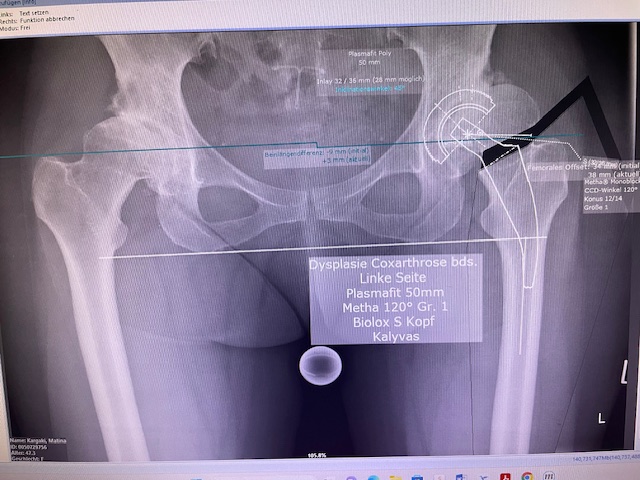

Ο προεγχειρητικός ψηφιακός σχεδιασμός

Ο προεγχειρητικός ψηφιακός σχεδιασμός ήταν ιδιαίτερα μεθοδικός και συγκεκριμένος. Η ακτινογραφία λεκάνης της ασθενούς εισήχθη σε ειδικό λογισμικό στον υπολογιστή, το οποίο επέτρεψε τον ακριβή προγραμματισμό της καινούριας θέσης της άρθρωσης.

Μέσω του ψηφιακού αυτού σχεδιασμού, υπολογίστηκε με ακρίβεια το μέγεθος και ο τύπος των προθέσεων, η γωνία του κώνου, καθώς και η σωστή ανατομική τοποθέτηση των μοσχευμάτων. ώστε να επιτευχθεί τέλειος ισοσκελισμός των κάτω άκρων και να αποφευχθεί οποιαδήποτε διαφορά μήκους μετεγχειρητικά!!!

Πρόκειται για ένα εξαιρετικά σημαντικό στάδιο, καθώς εξασφαλίζει τη μέγιστη δυνατή ακρίβεια, ταχύτητα και αποτελεσματικότητα κατά τη διάρκεια της επέμβασης. Επιπλέον, συμβάλλει στην άριστη λειτουργικότητα του ισχίου καθώς και να επιτευχθεί τέλειος ισοσκελισμός των κάτω άκρων και να αποφευχθεί οποιαδήποτε διαφορά μήκους μετεγχειρητικά!!!

Ο προεγχειρητικός ψηφιακός σχεδιασμός αποτελεί πάντα πλήρως εξατομικευμένο πλάνο, προσαρμοσμένο στα ανατομικά χαρακτηριστικά και τις ανάγκες του κάθε ασθενούς, και είναι καθοριστικός για την επιτυχία της επέμβασης !!!